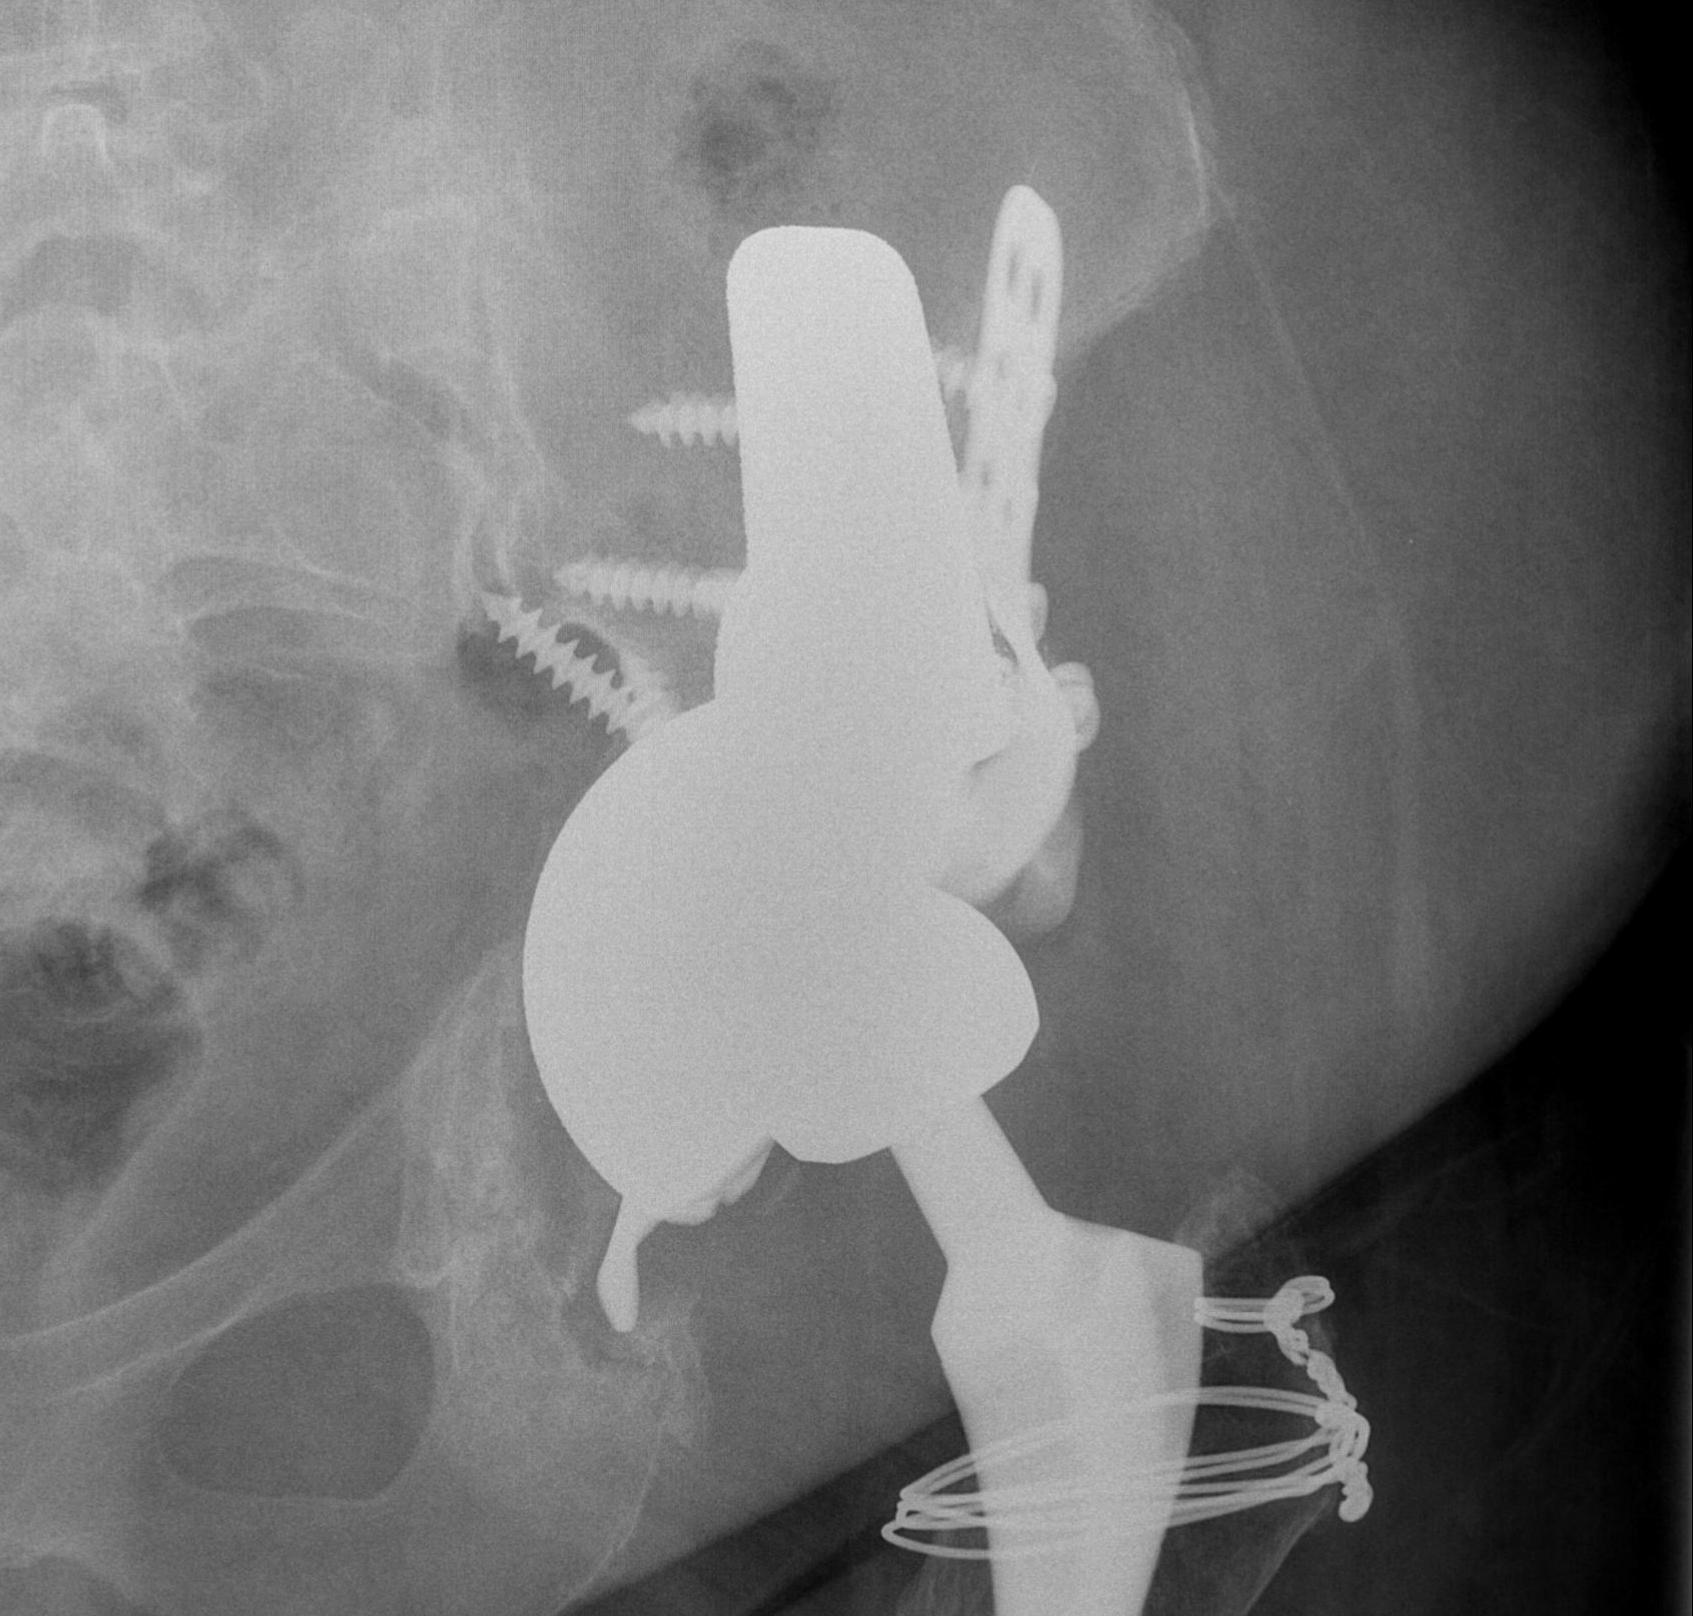

Option: Custom-made triflange components

CT guided model of pelvis

- custom made acetabular cage

- fits defect exactly

- flanges perfectly designed and not malleable to improve strength

- HA coated

- cement poly cup into it

Indications

- massive defects

Results

- 90% 4.5 year survival in complicated patients